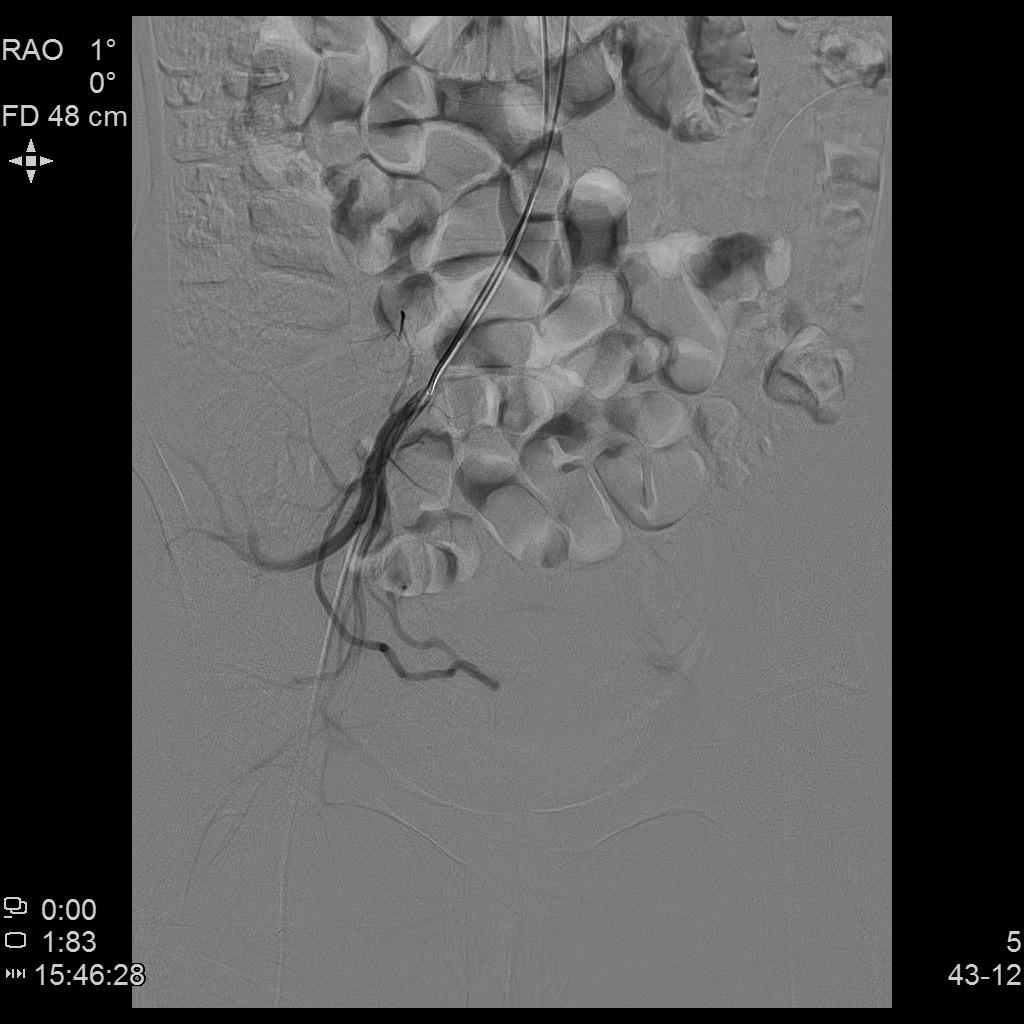

- 插管至右侧髂内动脉造影,显示右侧子宫动脉

- 插管至右侧子宫动脉,显示子宫右侧病灶情况

- 插管至左侧子宫动脉,显示子宫左侧病灶情况